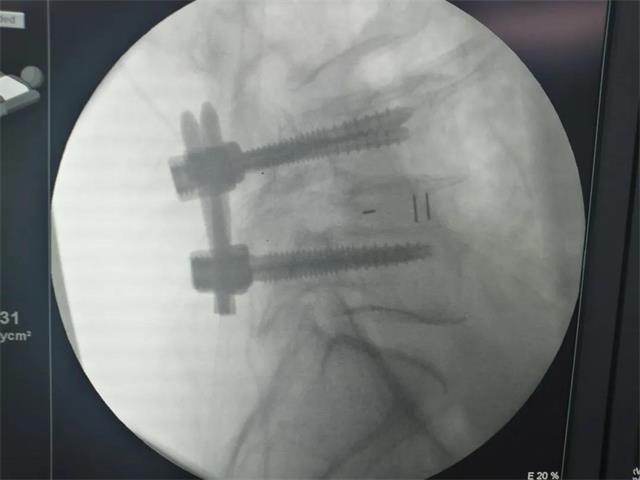

机器人经皮置钉

术后影像